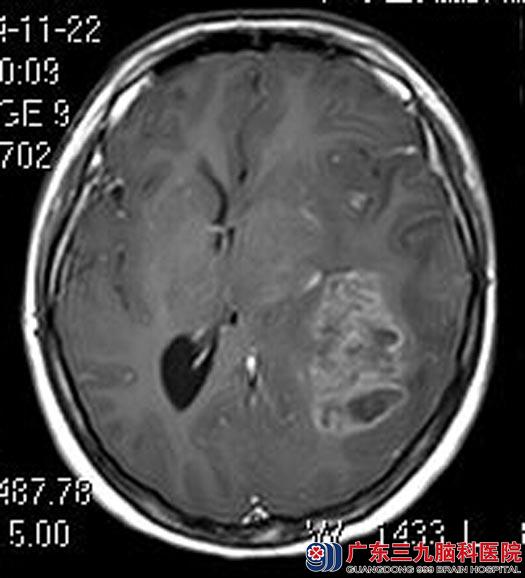

近2周以来出现双侧额颞部间断头痛,并逐渐加重,同时伴有呕吐,左眼视物模糊;当地医院头颅CT检查结果显示:左侧大脑半球占位性病变,考虑胶质瘤可能。梅梅没敢再拖延,立刻赶到广东三九脑科医院,行头颅MR检查提示:左侧颞岛顶叶为主占位病变,综合神经外科的鲁明主任考虑偏恶性肿瘤性病变,高级别星形细胞瘤或胶质母细胞瘤可能性大。

手术前